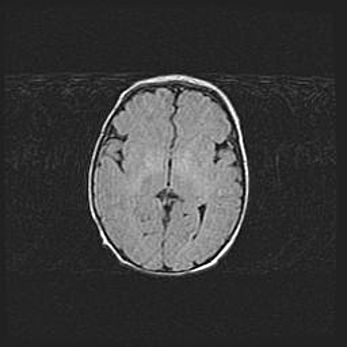

Церебральная ишемия II.

Возраст: 5 дней

Вес: 3400 г

Пол: женский

Окружность головы: 35 см

Срок гестации: 39 недель

Церебральная ишемия – это заболевание, характеризующееся недостаточностью (гипоксией) либо полным прекращением (аноксией) снабжения мозга кислородом по причине закупорки одного или нескольких сосудов. Это приводит к  что метаболическим расстройствам различной степени тяжести в тканях головного мозга, развитию коагуляционных некрозов и гибели нейронов.